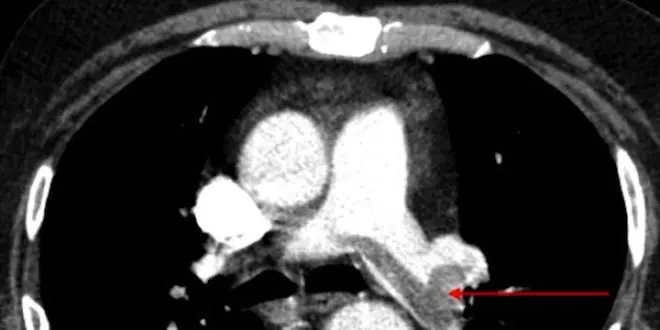

Lorsqu'un caillot de sang se forme et obstrue une veine, on parle de thrombose veineuse (ou phlébite). Dans 70% des cas, ce caillot ce détache et migre vers les artères pulmonaires, les obstruant à leur tour : c'est l'embolie pulmonaire.

- Embolie pulmonaire : une complication de la phlébite